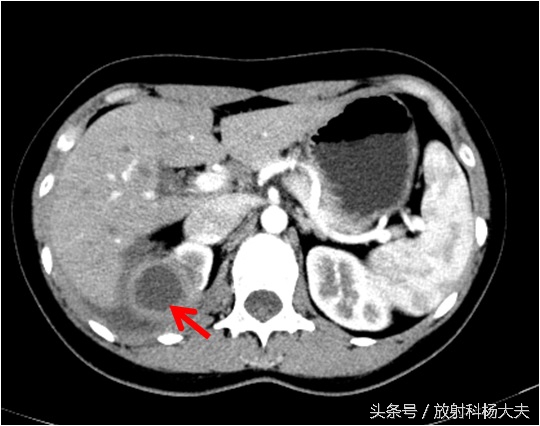

如下图,右肾上长了个东西,囊性的,壁挺厚。